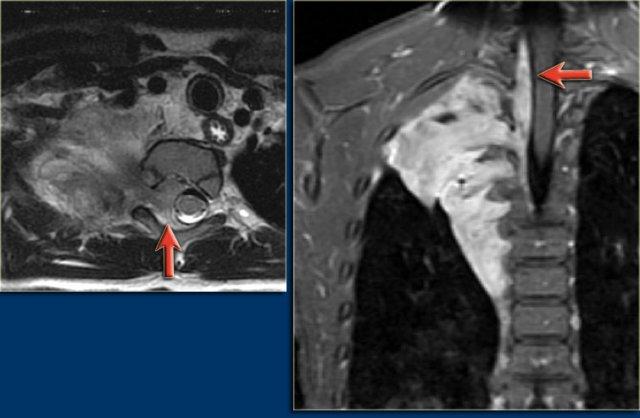

MRI ở bệnh nhân này cho thấy một khối nang ở cổ lan rộng vào hố nách phải và trung thất.

Khối u bao quanh các mạch máu.

MRI đôi khi có thể được sử dụng để xác định rõ hơn sự lan rộng của tổn thương.